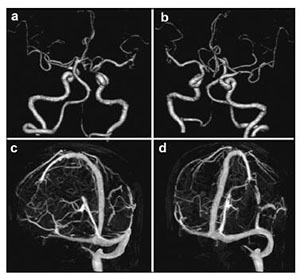

2 Case reportA 64-year-old man presented with a 2-month history of increasing headache, confusion, and progressive weakness on the left side limbs (grade 4/5). He had a past medical history of stent implantation owing to coronary heart disease and used aspirin as anti-platelet therapy. He had stopped the anti-platelet therapy one month prior owing to hematuria, which disappeared after cessation of aspirin. Brain computed tomography (CT) was performed after admission to our hospital, which revealed a hematoma with slight hyperdensity leading to a midline shift with compression of the right ventricle. The volume of the subdural hematoma was approximately 100 mL (Figure 1).

|

| Figure 1 Preoperative computed tomography images of the brain show a right side subdural hematoma without abnormal findings in the posterior fossa and right side frontal lobe. |